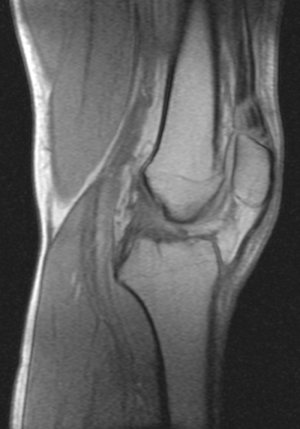

Недавно,5 сентября получил травму на работе. Выходя из транспорта почувствовал резкую боль с внутренней стороны колена (как бы ножом режет). Весь день не мог нормально поднять ногу. Особенно боль проявлялась при спуске по ступенькам. Через 3 часа после травмы обратился в травмпункт. Там сделали рентгенный снимок и сказали, что все впорядке. На следующий день весь коленный сустав с внешней стороны стал как бы после заморозки (холодить изнутри). Через дней 5-6 боль притупилась, а еще через несколько дней прошла. Но сустав все еще морозит изнутри. При резких движениях ощущения что кости сустава выходят и входят обратно на свое место. И сустав как будто чугунный. 8 октября сделал МРТ (так как большие очереди пришлось месяц прождать). Врач делавший МРТ сказал что дислокация коленной чашечки. К травмотологу только через неделю записан. Может подскажите что это? И последнее, сегодня начал морозить изнутри и сустав другой ноги. И холодок теперь идет от колена и вниз аж до пальцев на обеих ногах. Как бы онимения. Теперь не могу пробежать и нескольких метров такое ощущения что ниже колена мышцы как деревянные. Вот некоторые снимки МРТ. Рентген будет завтра на руках, если понадобится. Есть ли на самом деле смещение коленной чашечки?